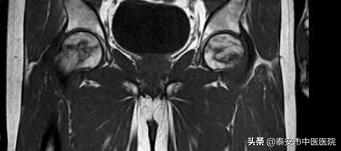

主治医生王乃舜介绍到,该患者双髋部疼痛活动受限4月余,有长期饮酒史,吸烟史,术前做了相关检查示双侧股骨头缺血性坏死(II期),考虑患者年龄偏高,保守治疗效果不佳,症状以疼痛活动受限为主,选择微创髓芯减压加支撑棒植入术对髋关节结构影响很小,最大限度减少病人的手术损伤,改善症状,延缓疾病进展,临床疗效十分满意。

术前诊断